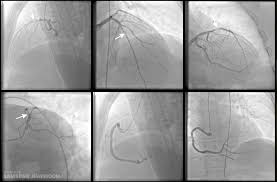

왼쪽 가슴 통증 원인 중에서 심장 질환은 특히 주의해야 할 부분입니다. 협심증이나 심근경색과 같은 심장 문제는 가슴 통증을 유발할 수 있으며, 이 경우에는 즉각적인 진료가 필요합니다. 심장 질환은 가슴 통증 외에도 호흡 곤란, 어깨나 팔로의 방사통 등의 증상을 동반할 수 있습니다. 따라서 왼쪽 가슴 통증이 심해지거나 다른 증상이 동반된다면 즉시 전문의를 찾아야 합니다.